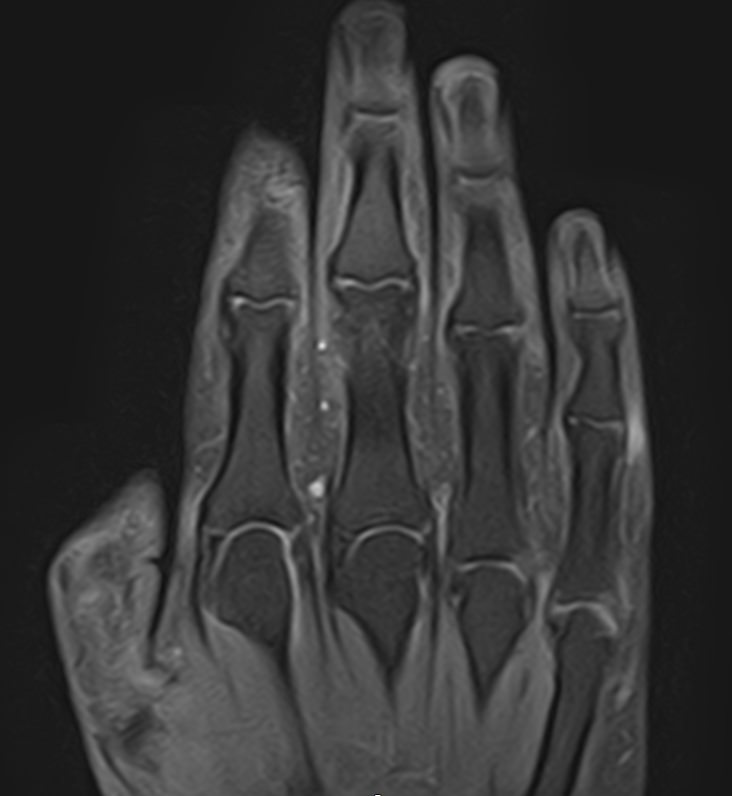

Современным и высокоточным методом диагностики заболеваний кистей рук является магнитно-резонансная томография. МРТ дает наиболее полную информацию о состоянии костей, суставов, связок, сухожилий, нервных волокон и мягких тканей кисти. Дополнительным преимуществом МРТ является ее безопасность, так как в основе метода лежит использование внешнего магнитного поля без применения ионизирующего излучения. При необходимости это позволяет выполнять исследование неоднократно в течение короткого периода времени.

Клиника «Доступная медицина» располагает новейшим 32-канальным высокопольным томографом закрытого типа TOSHIBA VANTAGE TITAN 1,5 Тесла, который позволяет получать изображения зоны кистей рук с высокой степенью детализации. Данные, полученные по результатам МР томографии, дают возможность врачу поставить точный достоверный диагноз и назначить своевременное лечение.

МРТ кисти руки – это высокоспецифичный метод визуализации мышц, связок, хрящей, костного мозга, жировой ткани.

С его помощью обнаруживаются:

• деструктивные изменения в суставах;

• утолщение синовиальных оболочек, выстилающих суставные полости;

• воспалительные выпоты ;

• краевые дефекты костной ткани;

• растяжения, разрывы связок , сухожилий сгибателей — разгибателей;

• субхондральные кисты (деградация кости вокруг суставного хряща);

• доброкачественные новообразования мягких тканей пальцев кисти (нодулярный теносиневит, сухожильный ганглий);

• злокачественные опухоли (остеосаркомы, мягкотканные саркомы ).

МРТ сухожилий и мягких тканей кисти руки помогает с постановкой окончательного диагноза, установленного при помощи других методик.